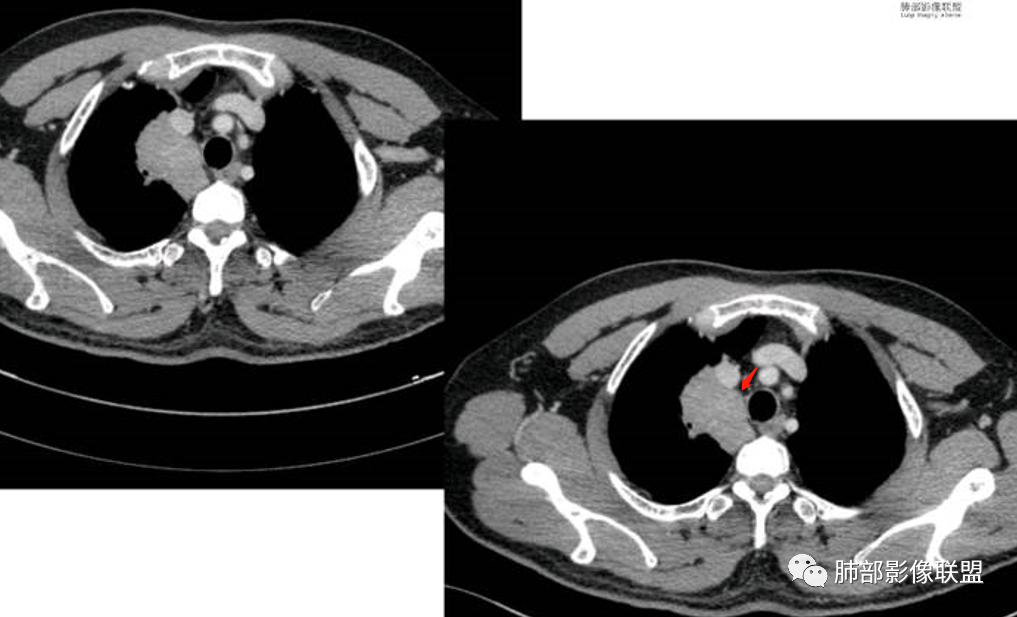

胸部CT:

中年男性,偶有咳嗽,右肺上叶近纵膈旁占位,内可见僵硬的支气管和小空泡征,病灶边缘可见分叶,毛刺,增强病灶中度以上不均匀强化,可见血管造影征,考虑恶性病变,腺癌可能性大。

右肺上叶纵隔胸膜侧一实性肿块,与纵隔胸膜宽基底相连,局部脂肪间隙消失,形态欠规则,内部可见多个小空泡,平扫密度尚均匀,增强后可见点条状强化,内部穿行血管,周围肺组织干净,纵隔淋巴结略肿大,男性44岁,只有咳嗽,考虑恶性肿瘤,腺癌,鳞癌。鉴别结核,OP,炎性假瘤。

右肺上叶近纵膈旁肿块,密度均匀,边缘分叶,毛刺,气管受压变窄,不均匀强化,可见血管造影征,考虑淋巴瘤,鉴别炎性假瘤。

中年男性,右肺上叶纵隔旁软组织肿块,边缘膨隆、毛糙,可见多发分叶,支气管穿行,部分截断,增强后密度欠均匀,纵隔内见多发小淋巴结,首先考虑恶性,腺癌,鉴别淋巴瘤

中年男性,右肺上叶纵隔旁肿瘤,稍膨隆,有毛刺,支气管穿行,远端闭塞,强化均匀,血管走行尚可,考虑淋巴瘤可能性大(支气管远端闭塞,不太符合),鉴别腺癌(气管穿行后闭塞,不太符合),op(病灶稍膨隆)

患者中年男性,咳嗽就诊,无其他不适。胸部CT:右肺上叶尖段上纵膈旁肿块,边界清楚,边缘光滑,内见支气管受压变窄,伴阻塞性改变,增强均匀强化,见血管造影征。综合考虑恶性病变,小细胞肺癌或淋巴瘤。气管镜活检应能明确。

中年男性,右肺上叶纵隔旁实性病灶,边缘有彭隆,有平直,有分叶,有尖角,病灶边缘中心可见支气管征,周围少许磨玻璃,边缘模糊,增强后动脉期病灶可见强化血管影,渐进性强化,临近血管界限清晰。考虑炎性病灶,普通炎性肉芽肿?结核?炎性肌纤维母细胞瘤?鉴别腺癌,淋巴瘤